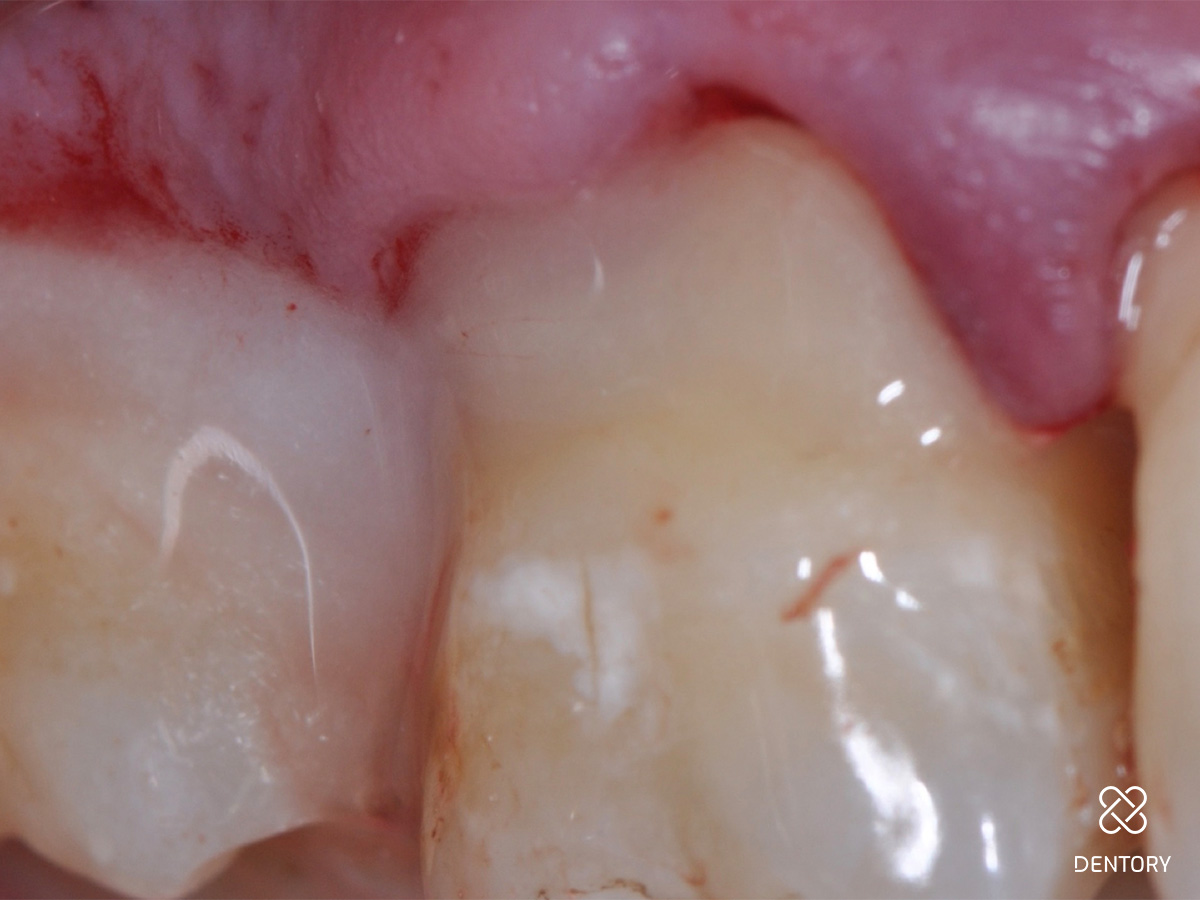

Abbildung 1

Ausgangssituation: Frontalansicht.